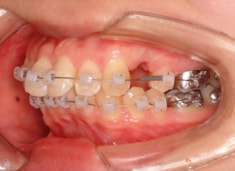

治療開始時

治療開始から1年7ヶ月後